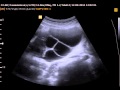

В настоящее время существуют различные методы и технологии для определения беременности. Наиболее распространенными из них являются использование домашних тестов на определение ХГЧ, ультразвуковое исследование, анализы крови на определение определенных беременностей гормонов и другие методы, которые позволяют точно определить наличие или отсутствие беременности.